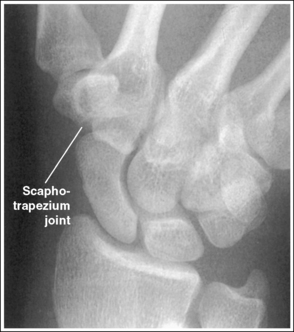

The scaphotrapezium and scaphotrapezoidal joint spaces are open.

• The scaphotrapezium and scaphotrapezoidal joints are aligned at a 15-degree angle to the IR when the patient's hand is in full extension. These joints will be open when a 15-degree proximally angled central ray is used. If the hand is not extended so that the palm is placed flat against the IR, but rather is flexed, the second metacarpal is superimposed over the trapezoid and trapezium and closes the scaphotrapezium and scaphotrapezoidal joint spaces (see Image 55).